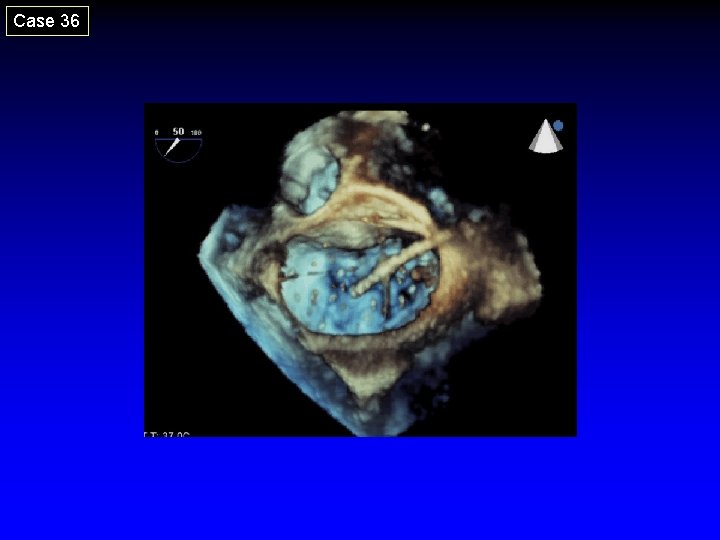

Case 36